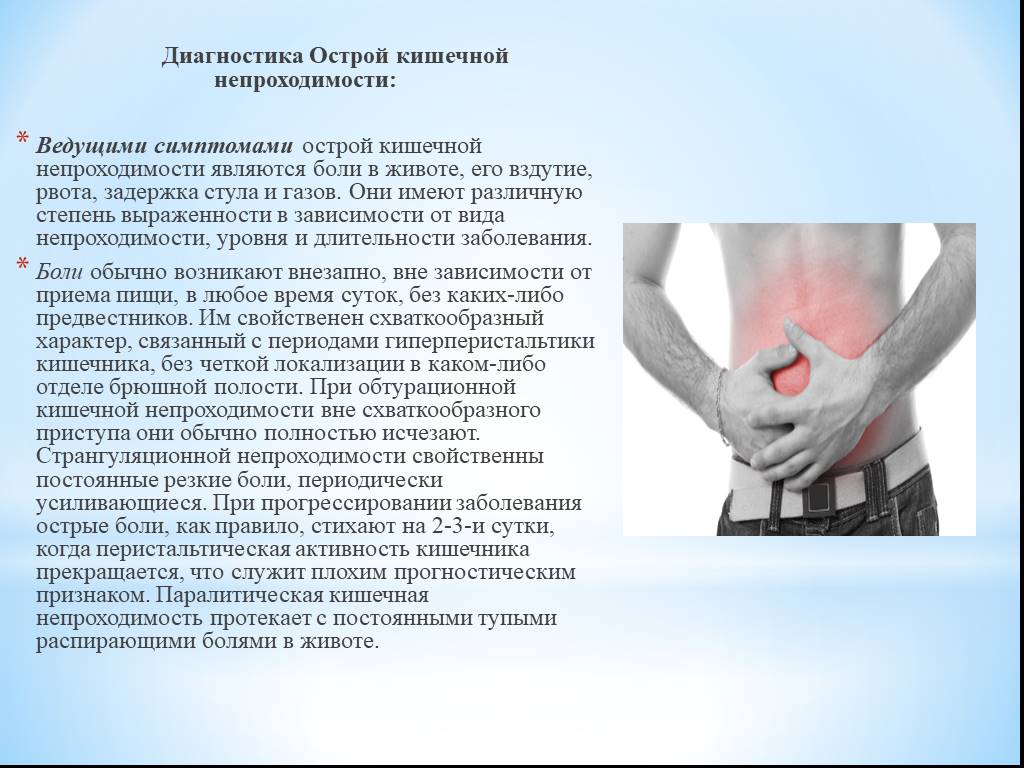

Иллюстрации и информация о симптомах острого кишечного непроходимости

Раздел: Кадры-советчики